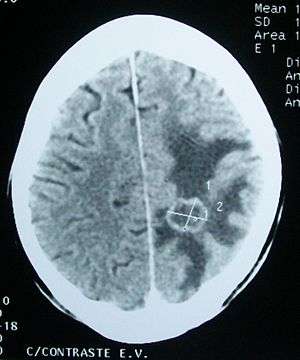

| Edema (darker areas) surrounding a secondary brain tumor. | |